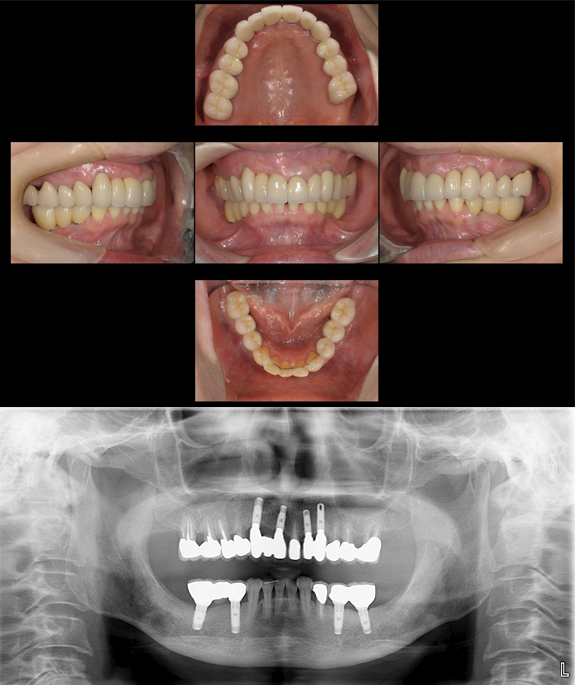

症例2

術前

「食事を美味しくしたい。」ということで来院されました。お口の中はほとんど前歯の噛み合わせしかありません。義歯は作ったけれど合わずに全く使ってないそうです。

術後

インプラントでしっかりとした奥歯を作ることで、なんでも美味しく食べることができるようになりました。